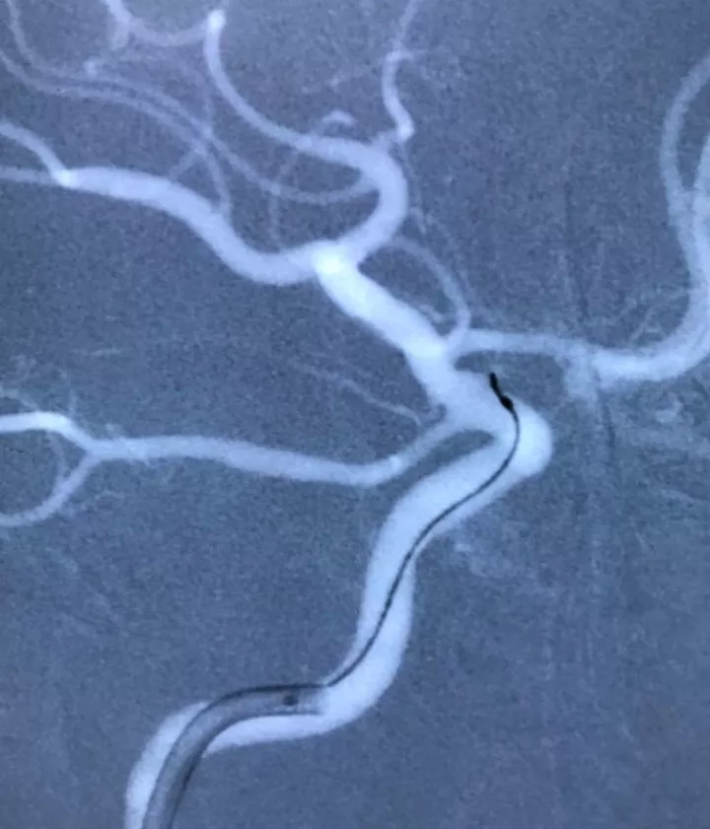

右颈内动脉工作位造影

微导丝头端进入瘤颈